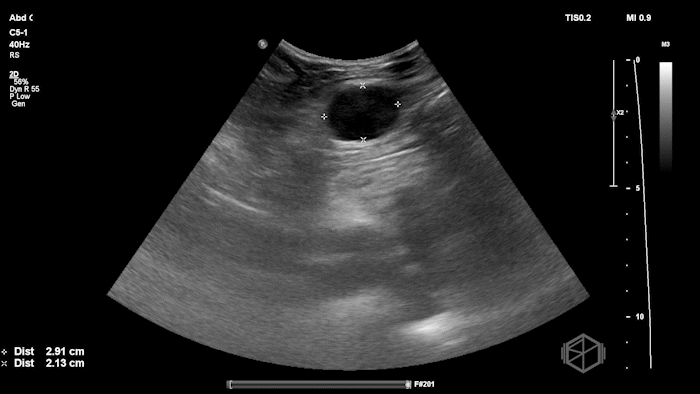

Given the patient’s focal abdominal wall tenderness, a POCUS exam of the left lower quadrant at the point of maximal pain was performed.

She obtained the following images:

The POCUS shows an hypoechoic circular mass within the rectus muscle. There is no active color doppler flow suggesting likely no active bleeding.

Diagnosis: Rectus sheath hematoma (RSH)